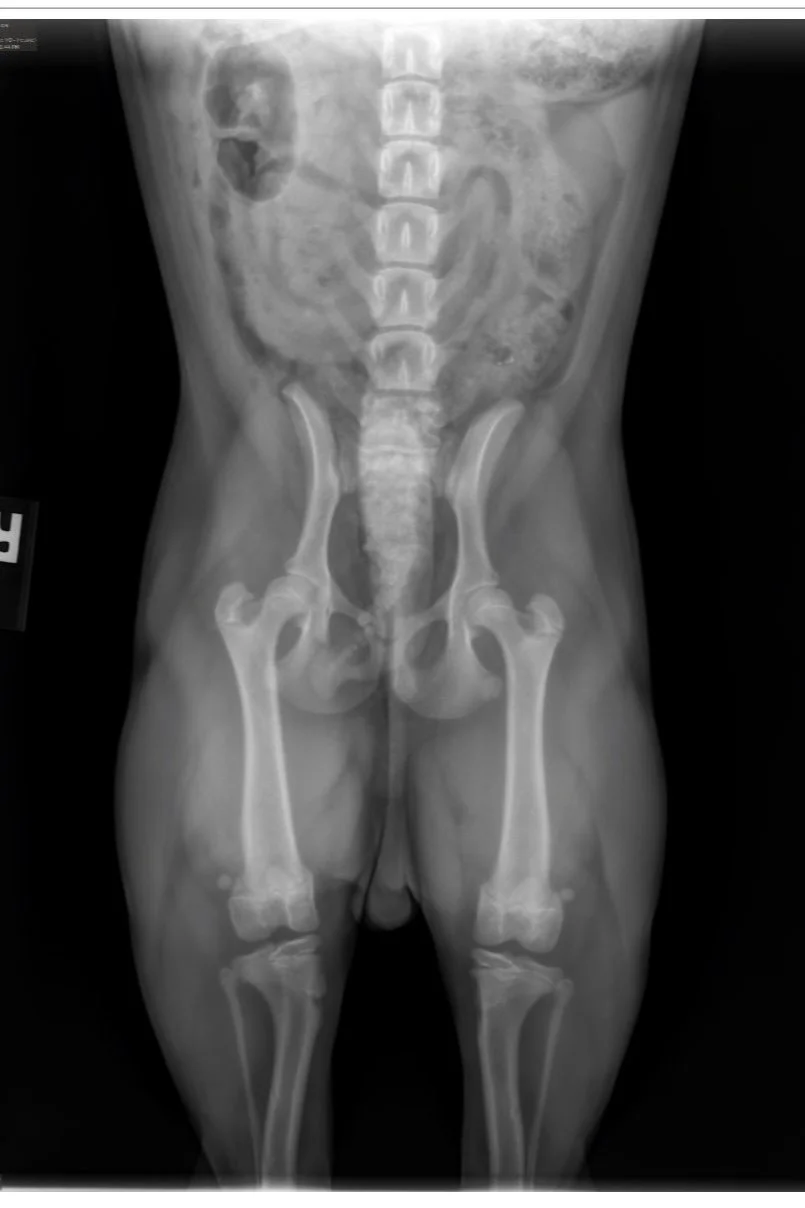

L’OFA recommande de faire des tests de biomécanique du chien: Dysplasie de la hanche, Luxation des rotules, Examen oculaire, évaluation cardiaque, Coude, Thyroïdite, et Trachée.

Tous ces tests doivent être fait par des vétérinaires et certains laboratoires accrédités. La vérification de l’enregistrement original du chien AKC et de l’identification par micropuce ou tatou est obligatoire pour que le vétérinaire puisse signer et envoyer les radiographies de façon électronique, de la clinique vétérinaire à L’OFA et ainsi éviter les fraudes.

L'OFA est un organisme à but non lucratif situé aux États-Unis qui permet de publier les résultats des tests fait par les vétérinaires et les laboratoires accrédités. 3 vétérinaires indépendants spécialisés, évaluent les radiographies et leurs donnent des “quotes”. C’est une excellente façon de prouver qu’un éleveur a le souci de dépister des problèmes potentiels sur les animaux qu’il prévoit reproduire, et de montrer au public les résultats des épreuves complétées. Comme la majorité des gens ne sont pas spécialisés en lecture de radiographies, les notes données par L’OFA sont impartiales et permettent d’avoir une vraie vue d’ensemble.

Pour la méthode traditionnelle, celle de l’OFA (Orthopedic Foundation for Animals), une seule radiographie est prise. Avec la méthode PennHIP, ce sont trois prises de vues qui sont réalisées. Elles permettent au vétérinaire de détecter la présence d’arthrose dans l’articulation et de calculer le degré de relâchement (s’il y en a un). Le PennHIP peut être effectué à partir de l’âge de 16 semaines, ce qui en fait une méthode de dépistage précoce. La dysplasie de la hanche est une maladie génétique qui affecte les chiots dès leur plus jeune âge.